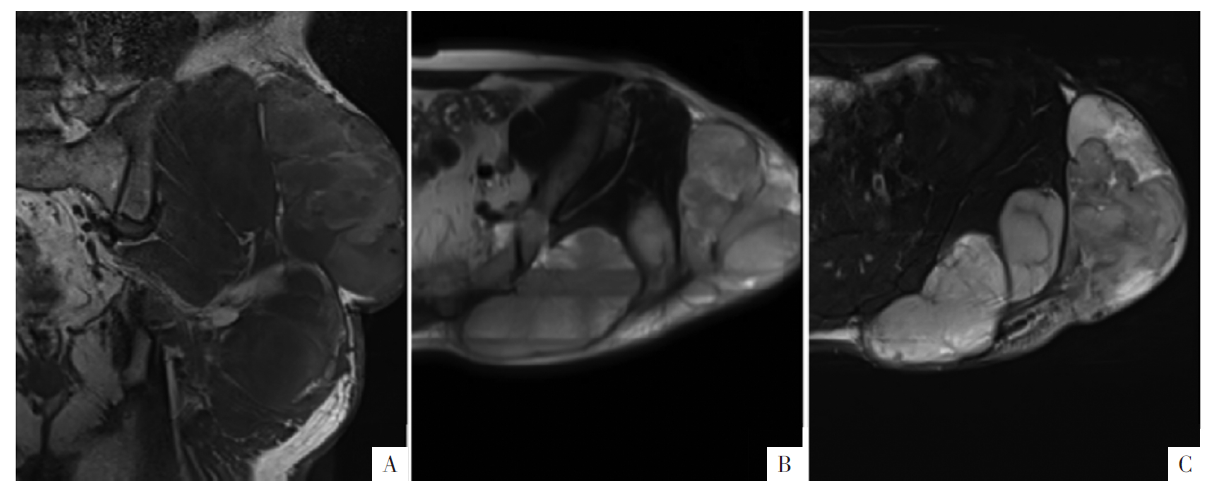

图7

病人男,56岁,左侧髋部软组织MLPS。A—C图分别为冠状面T

1

WI、横断面T

2

WI、T

WI-FS,显示软组织团块状、大理石样外观,T

WI-FS呈混杂信号,T

WI呈高信号。